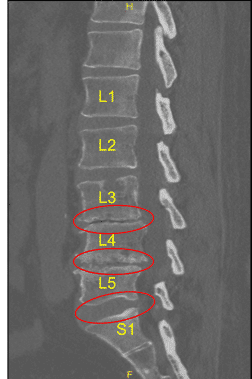

Postoperative X-ray Saggital View

Postoperative X-ray Sagittal View

Postoperative X-ray